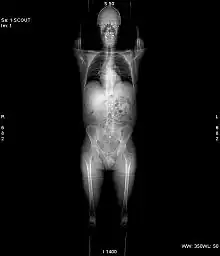

X-ray computed tomography operates by using an X-ray generator that rotates around the object; X-ray detectors are positioned on the opposite side of the circle from the X-ray source.

In conventional CT machines, an X-ray tube and detector are physically rotated behind a circular shroud (see the image above right). An alternative, short lived design, known as electron beam tomography (EBT), used electromagnetic deflection of an electron beam within a very large conical X-ray tube and a stationary array of detectors to achieve very high temporal resolution, for imaging of rapidly moving structures, for example the coronary arteries. Systems with a very large number of detector rows, such that the z-axis coverage is comparable to the xy-axis coverage are often termed cone beam CT, due to the shape of the X-ray beam (strictly, the beam is pyramidal in shape, rather than conical). Cone-beam CT is commonly found in medical fluoroscopy equipment; by rotating the fluoroscope around the patient, a geometry similar to CT can be obtained, and by treating the 2D X-ray detector in a manner similar to a CT detector with a massive number of rows, it is possible to reconstruct a 3D volume from a single rotation using suitable software.